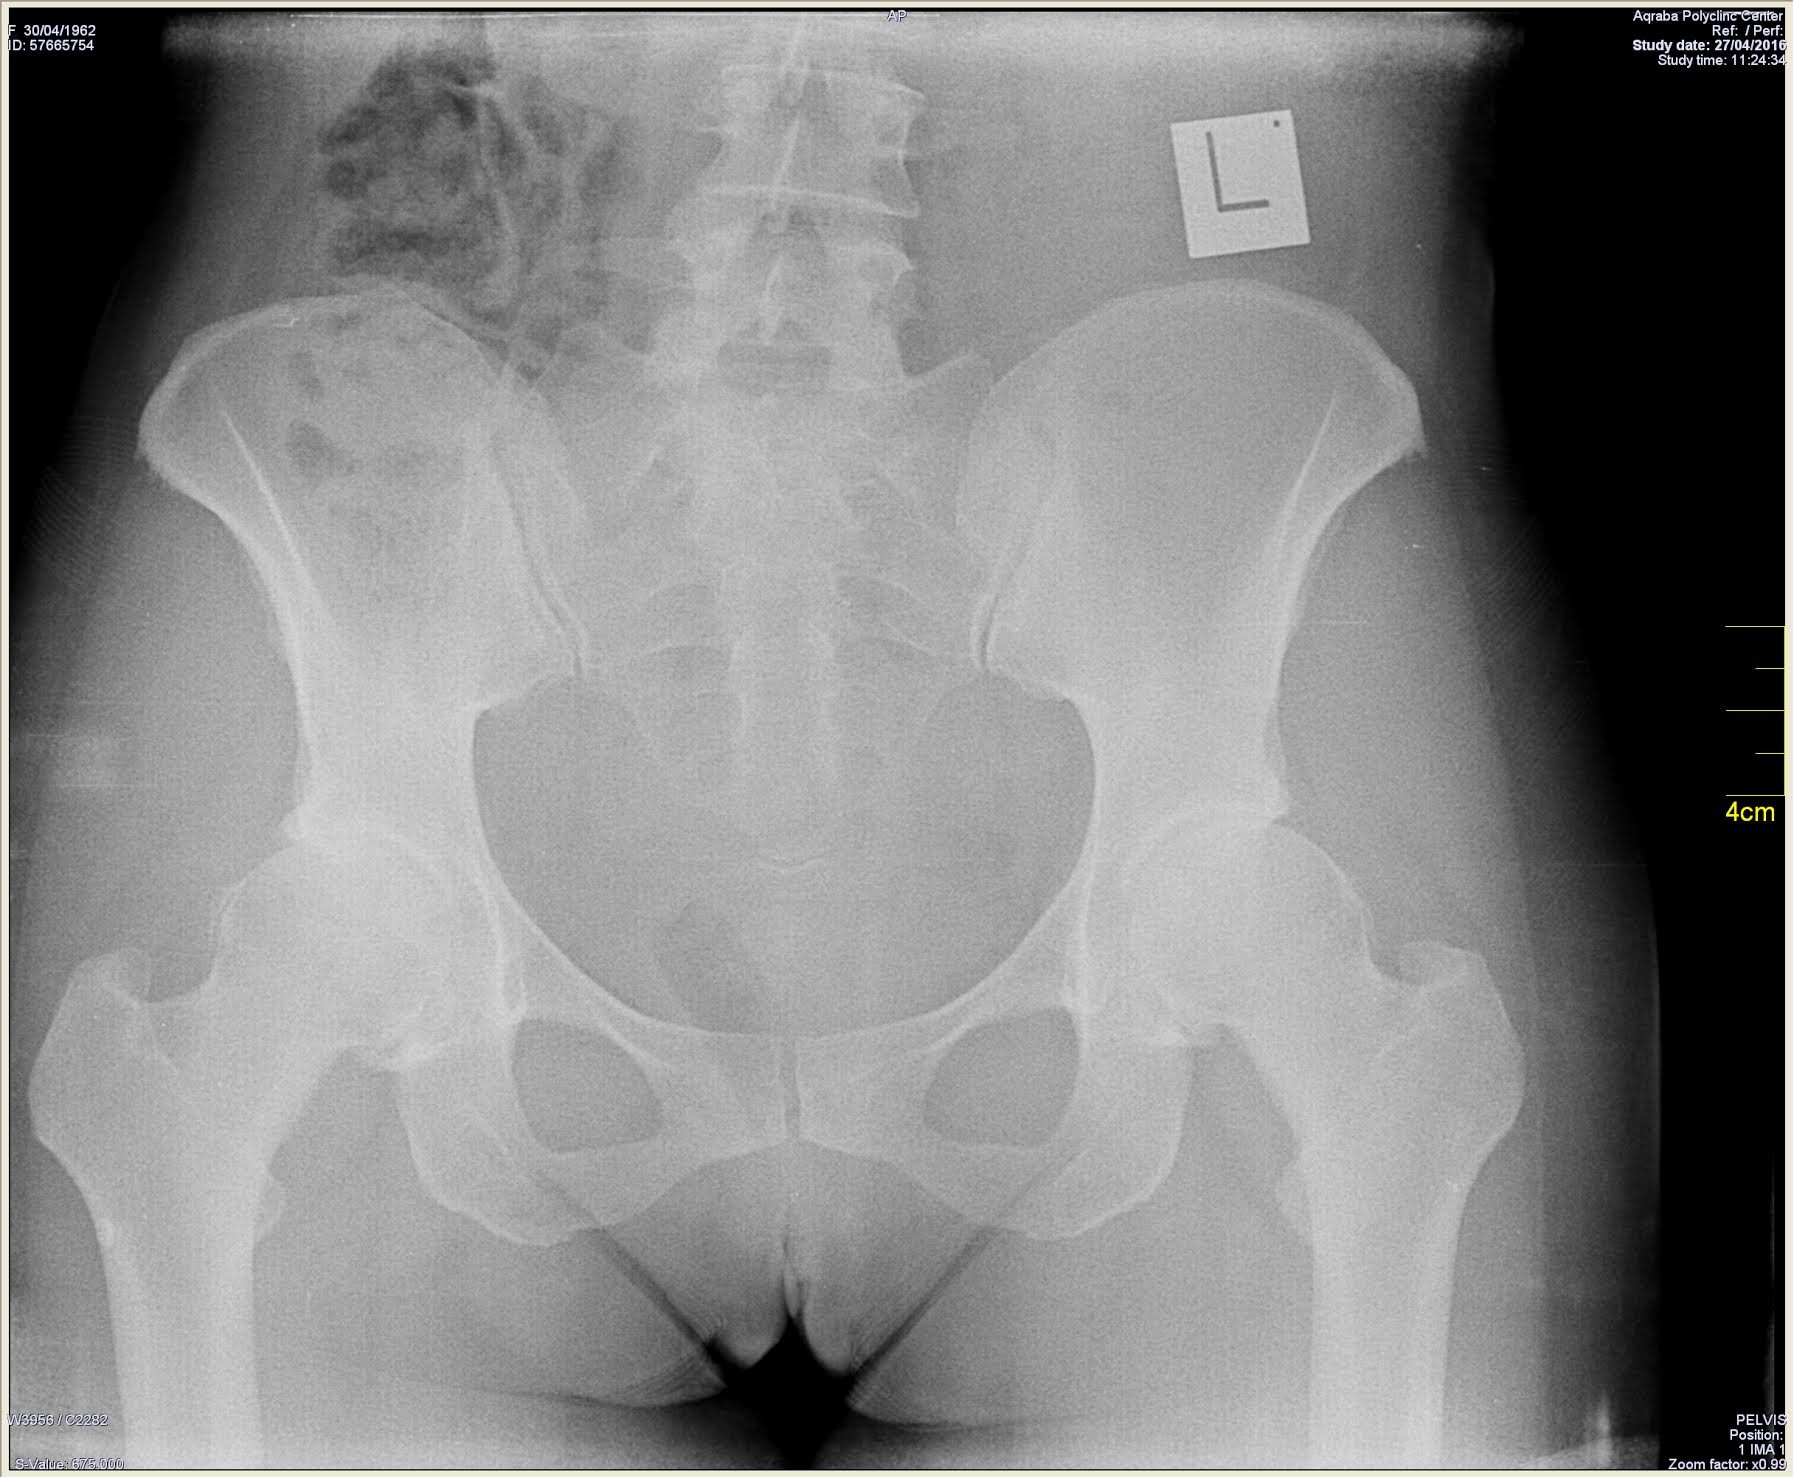

צילום רנטגן פשוט X-RAY הדרך המקובלת לאבחן שחיקת סחוסים ועוות של המפרק.

המאפיינים של סחוס מפרק שחוק בצילום רנטגן כוללים:

- הצרה של המרווח המפרקי

- אוסטאופיטים היווצרות של עצם סביב המפרק

- הסתיידויות וציסטות נוצרות מתחת לסחוס המפרקי באזורי החיכוך בין העצמות